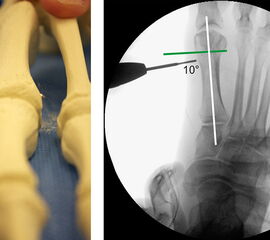

Präoperatives Röntgenbild Fuß d.p. mit eingezeichneten Winkeln. A) Intermetatarsalwinkel, B) Hallux valgus Winkel, C) Interphalangeal-Winkel.

Abbildung 2

• Operationsplanung anhand der Röntgenaufnahmen unter Beachtung wichtiger radiologischer Landmarks wie Intermetatarsalwinkel, Hallux valgus – Winkel, distaler Gelenkflächenwinkel (Distal Metatarsal Articular Angulation - DMAA), Metatarsaleindex und Sesambeinposition (Abb. 2).